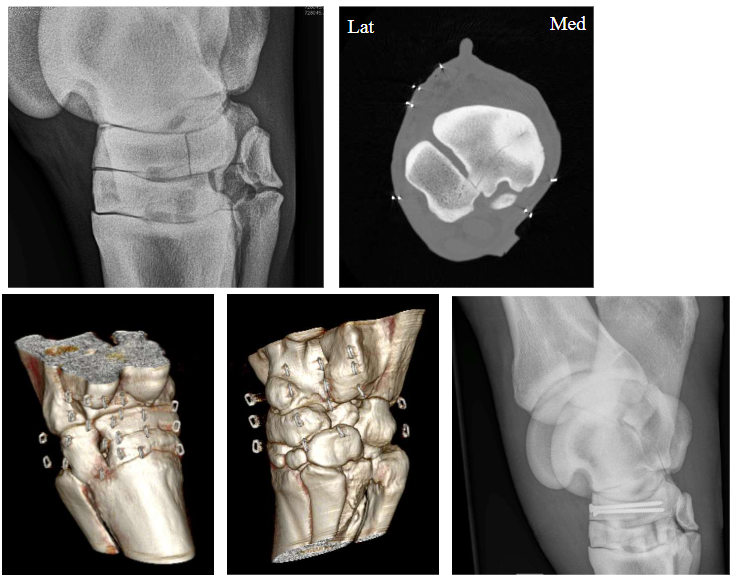

Vorm van de fractuur + fragmentatie?

Meervoudig

Enkelvoudig

longitudinaal in het saggitaal vlak

Intra-articulair in de beide gewrichten, verbrijzeld

Er is geen intact struct → slechte prognose